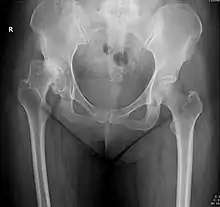

Crowe classification

In 1979 Dr. John F. Crowe et al. proposed a classification to define the degree of malformation and dislocation. Grouped from least severe Crowe I dysplasia to most severe Crowe IV.[13] This classification is very useful for studying treatment results.

Rather than using the Wiberg angle because it makes it difficult to quantify the degree of dislocation they used 3 key elements to determine the degree of subluxation: A reference line at the lower rim of the "teardrop", junction between the femoral head and neck of the respective joint and the height of the pelvis (vertical measurement). They studied anteroposterior pelvic x-rays and drew horizontal lines through the lower rim of a feature called "teardrop". The distance between this line and the middle lines of the junction between femur head and neck gave them a measure of the degree of femur head subluxation. They further established that a "normal" diameter of the femur head measures 20% of the height of the pelvis. If the middle line of the neck-head junction was more than 10% of the pelvis height above the reference line they considered the joint to be more than 50% dislocated.[13]

The following types resulted:[13]

| Class | Description | Dislocation |

| Crowe I | Femur and acetabulum show minimal abnormal development. | Less than 50% dislocation |

| Crowe II | The acetabulum shows abnormal development. | 50% to 75% dislocation |

| Crowe III | The acetabula is developed without a roof. A false acetabulum develops opposite the dislocated femur head position. The joint is fully dislocated. | 75% to 100% dislocation |

| Crowe IV | The acetabulum is insufficiently developed. Since the femur is positioned high up on the pelvis this class is also known as "high hip dislocation". | 100% dislocation |